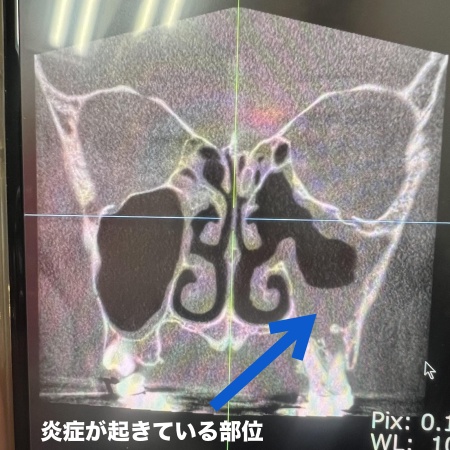

50代女性 歯根の細菌感染が原因で生じた歯性上顎洞炎を精密根管治療で改善した症例

- 根管治療

- 治療期間の目安 約5週間

- 治療回数の目安 -

- 治療費総額の目安 約120,000円

治療のリスク

・まれに根管治療後も再治療、外科手術、抜歯などの処置が必要となる場合があります ・治療中まれに器具の破折、被せ物や詰め物など修復物の損傷、歯の破折が起こる場合があります ・治療中や治療後に不快症状が出たり、治療後に痛みや腫れなどが生じたりする可能性があります ・一部の治療を除き、自費診療(保険...

by.海谷歯科医院

2026/03/30